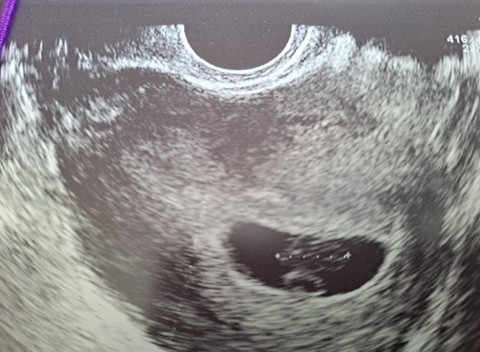

Hej, jestem po 6 poronieniach na etapie 5/6 tygodnia. Niepłodność immunologiczna w skrócie. Obecnie jestem w 7 ciąży, stwierdzona przez ginekologa, beta była książkowa, zarodek o parę dni młodszy na USG, bicie serca 170. Wręcz książkowo, jestem na żelaznym zestawie. Obecnie jestem w 10 tyg. Do rzeczy. Kupiłam detektor dla spokojności...no właśnie.